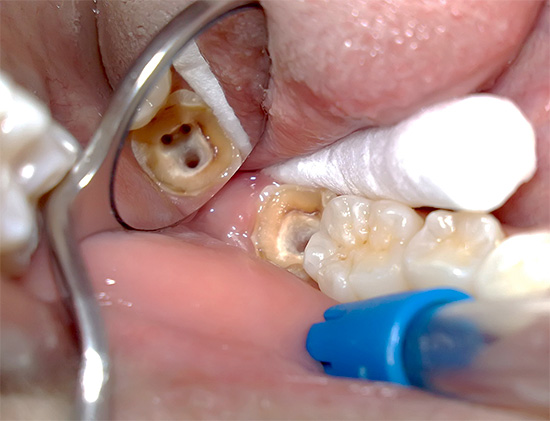

La foto sotto mostra un dente in cui la carie profonda ha portato allo sviluppo della pulpite:

Molte persone conoscono in prima persona la possibile comparsa del cosiddetto "flusso" (periostite). Ma poche persone sanno che il flusso sulla gomma appare spesso dopo un prolungato dolore alla polpite ed è il risultato della morte del "nervo" nel canale dentale con la formazione di pus, che semplicemente non ha nessun posto dove andare, e quindi va al lato della radice del dente, gonfiando la gomma.